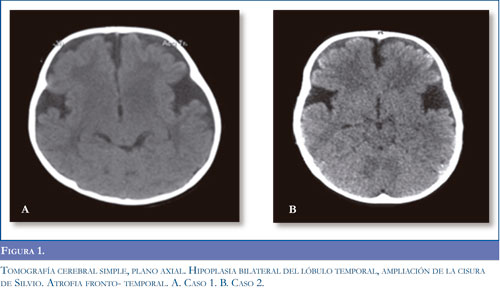

Caso 3. Escolar masculino producto de segunda gestación, controles prenatales normales, parto espontáneo, al nacer APGAR bajo y síndrome de dificultad respiratoria que requirió ventilación mecánica con evolución satisfactoria. Sostén cefálico a los 2 meses, sedente a los 6 meses; a los 9 meses presentó cuadro febril secundario a infección respiratoria alta que requirió hospitalización donde se documentó luego del cuadro viral pérdida de las habilidades adquiridas en el neurodesarrollo. Se valoró meses después en consulta de neuropediatria, se solicitó RM cerebral que mostró atrofia cortical difusa con quistes aracnoideos bilaterales temporales (Figura 3), se sospechó enfermedad metabólica y se solicitó cromatografía de aminoácidos en orina y plasma reportados normales, cromatografía de ácidos orgánicos en orina donde se documentó excreción elevada de ácido glutárico y de 3 hidroxiglutárico. La confirmación diagnóstica se realizó a los 18 meses de edad y se inició manejo nutricional con restricción proteica, multivitaminas y suplementación con L-carnitina y plan de habilitación. Presentó múltiples episodios de descompensación metabólica por manejo nutri-cional irregular, cuadros febriles, cursó con eventos de microaspiración y pérdida progresiva de peso, se realizó gastrostomía a los 2,5 años de edad. La enfermedad progresó clínica e imagenológicamente con aumento de las crisis distónicas sin respuesta a manejo farmacológico y fiebre de origen central. En la actualidad cursa con cuadriparesia discinética, retardo mental profundo. Evaluación funcional motora nivel V, 10,4%.

La sospecha clínica fue apoyada en todos los pacientes con imágenes típicas de atrofia frontotem-poral bilateral conocidas como "alas de murciélago" en la tomografía axial computadorizada y por alteraciones de la sustancia blanca en grados variables en la resonancia magnética cerebral como se describe en la literatura (11).